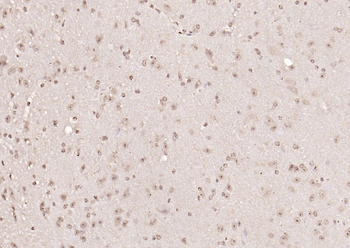

- PPM1D Rabbit Polyclonal Antibody [orb704535]Featured

IF, IHC-Fr, IHC-P

Human, Mouse, Rat

Mouse, Rat

Rabbit

Polyclonal

Unconjugated

100 μl, 50 μl, 200 μl - HSC70 Mouse Monoclonal Antibody [orb704174]Featured